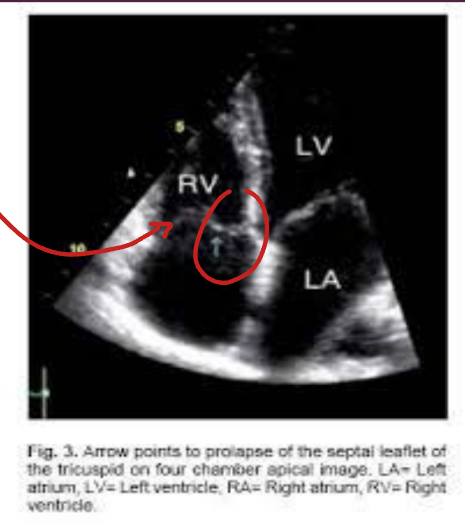

What is tricupsid valve prolapse? (TVP)

The prolapse of any part of the TV leaflets beyond the TV annulus.

What is the most common TV leaflets to prolapse?

The anterior leaflet.

Using 2-D, what view demonstrates the anterior and septal leaflets of the TV?

A4.

TVP is indicative if leaflets proplase past TV annulus superiorly by how much?

> 2 mm.